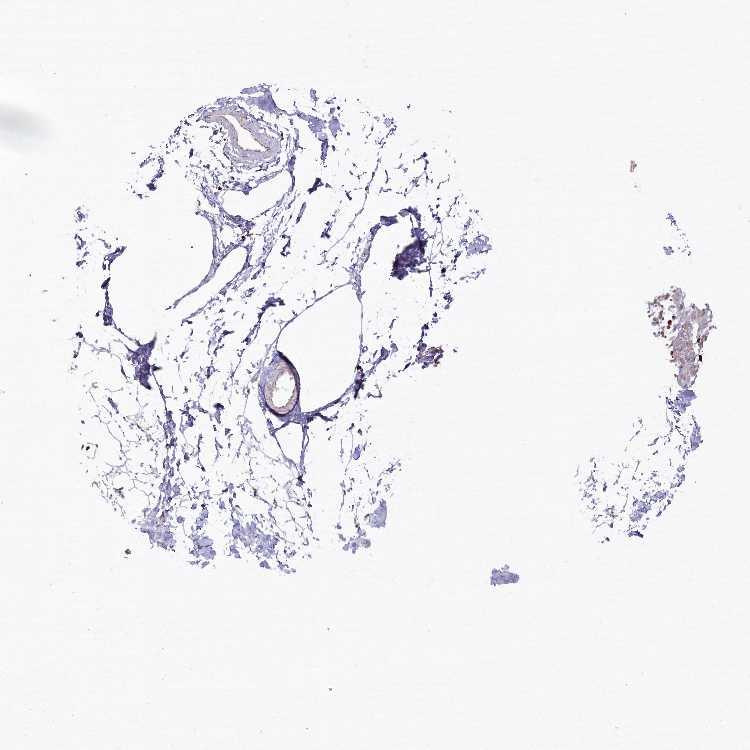

SOFT TISSUE 2 - Antibody stainingi

Antibody staining in the annotated cell types in the current human tissue is reported as not detected, low, medium, or high, based on conventional immunohistochemistry profiling in selected tissues. This score is based on the combination of the staining intensity and fraction of stained cells.

Each image is clickable and will lead to virtual microscopy that enables deeper exploration of all samples and also displays staining intensity scores, fraction scores and subcellular localization as well as patient and tissue information for each sample.

Antibody HPA037770Antibody HPA037771

Fibroblasts Not detectedMedium

Peripheral nerve Not detectedNot detected